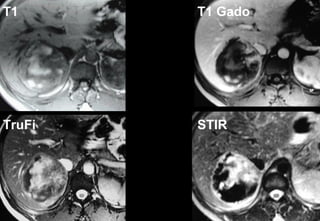

T1 T1 Gado

TruFi STIR

Adénome - IRM